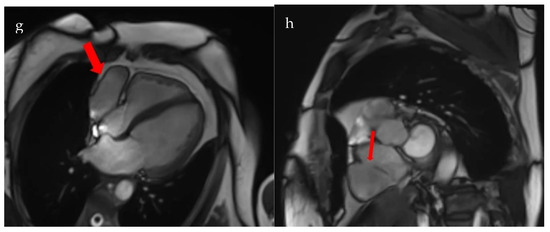

The patient underwent coronary angiography to exclude an ischemic cause of the dyspnea. Coronarography showed normal epicardial coronary arteries (Figure 2).

Figure 2.

Normal coronary angiogram. (a). Right coronary artery; (b). Left main coronary artery, anterior descending artery, circumflex artery, and collateral branches.